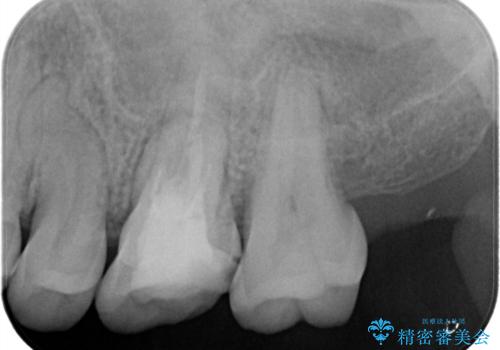

【見逃し根管を発見】根管治療〜セラミッククラウン

- 他院で根管治療した歯の再治療を希望されて来院されました。

未処置の根管があったため、マイクロスコープにて観察したことで、見逃しの根管を含めて清掃・充填を行うことができました。

上顎第一大臼歯は基本的に4根管です。